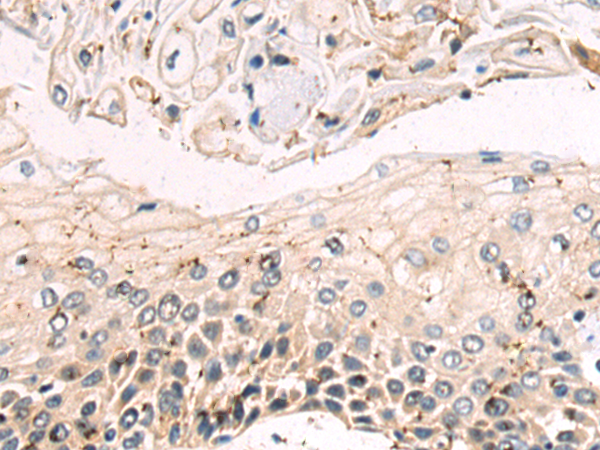

分类: 科研抗体货号: P09637别名: p10; PCH1B; RRP40; Rrp40p; CGI-102; hRrp-40; bA3J10.7应用: IHC反应种属: Human, Mouse